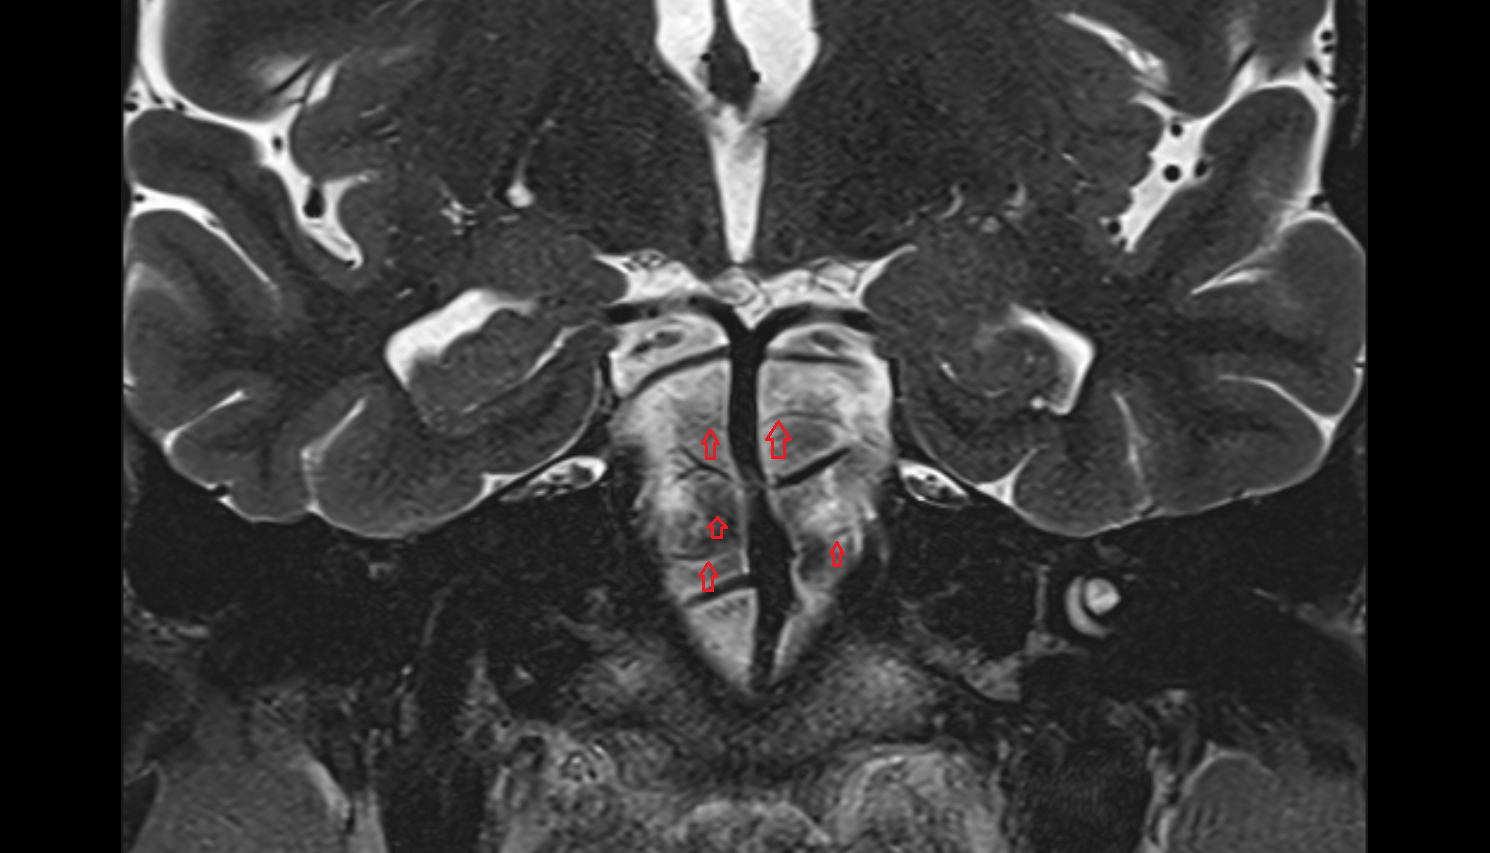

- Body of hippocampus

- Head of hippocampus

- Tail of hippocampus

- Hippocampus